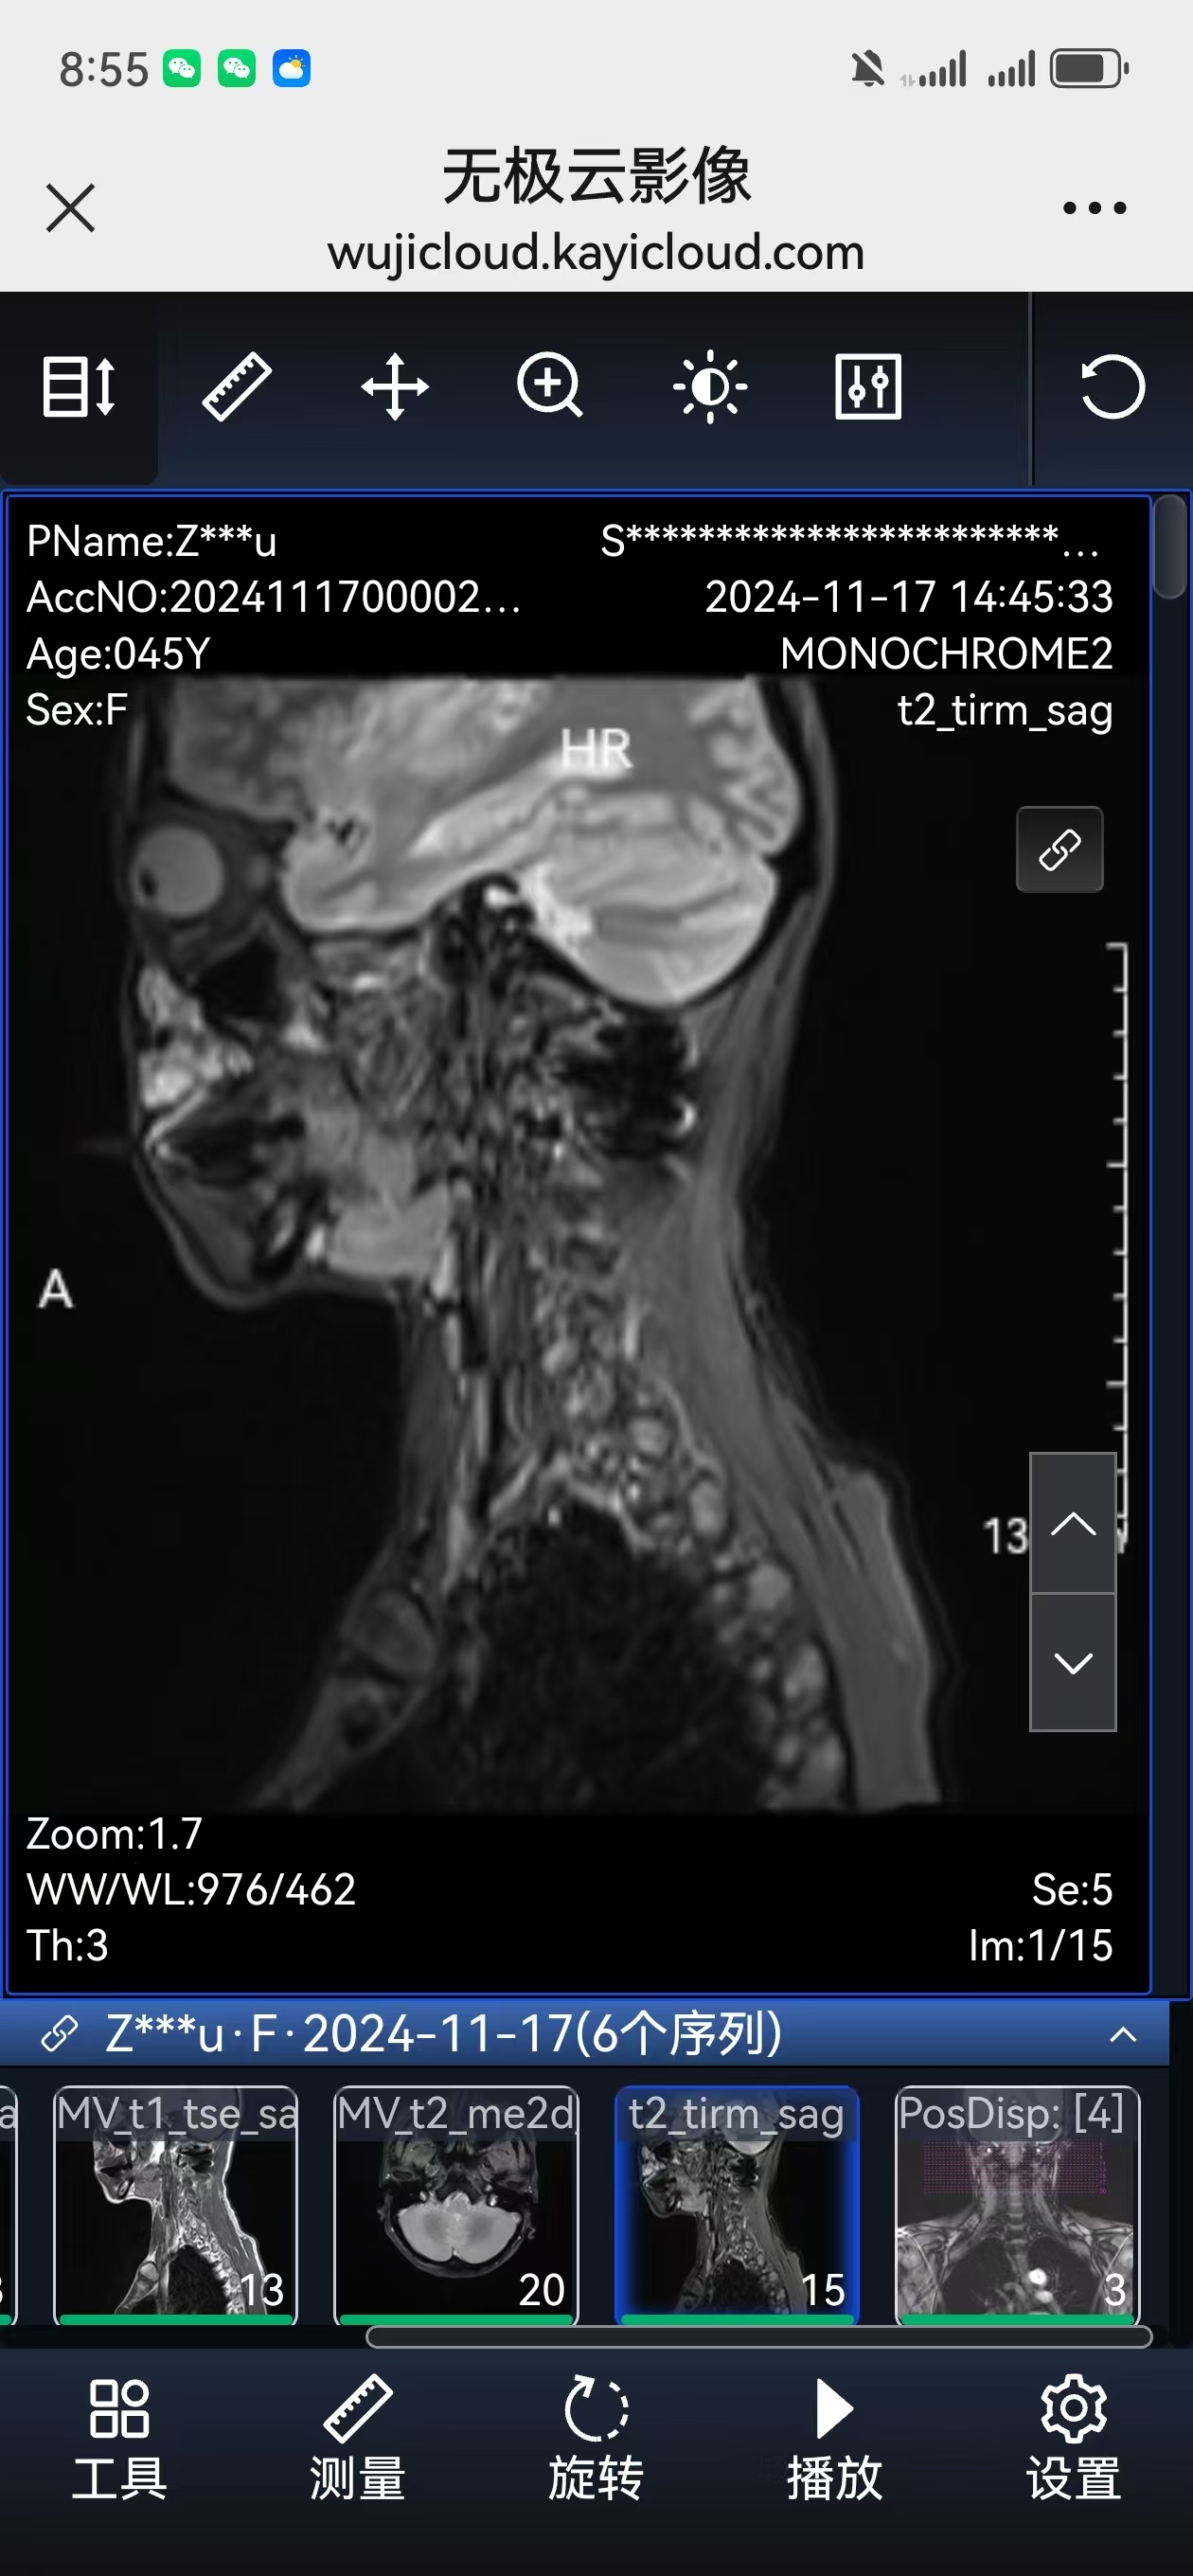

• 术后影像:

• 2024.11.07,复查,对位良好。